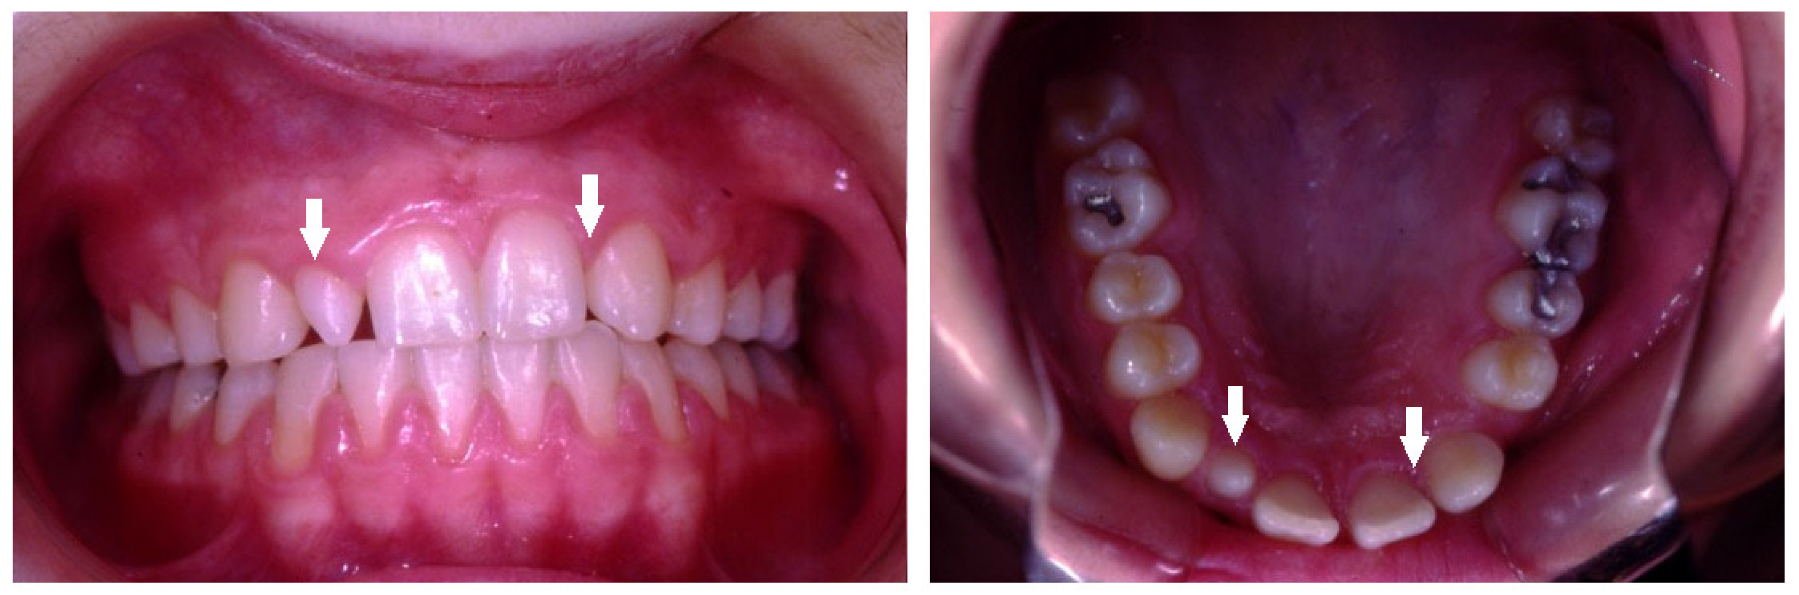

| Supernumerary | Presence of extra teeth more than the full complement of teeth. |

| Transposition | Two adjacent permanent teeth that switched their position within the same quadrant of the dental arch. |